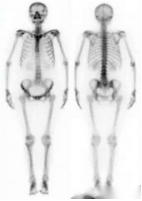

正常骨显像